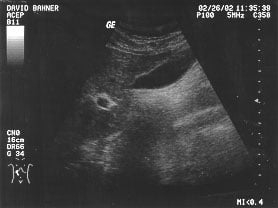

Gallbladder (unlabeled)